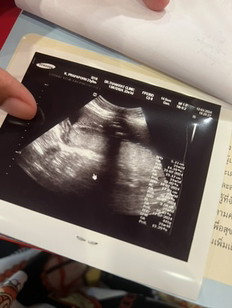

สวัสดีค่ะ ภาพแรกหนู9wเองคับ ภาพทที่2 หนู จะ18wแล้ว เห็นอวัยวะศรีษะและก็ขาหมดแล้วคับพี่ๆน้าๆ 👶🏻💗